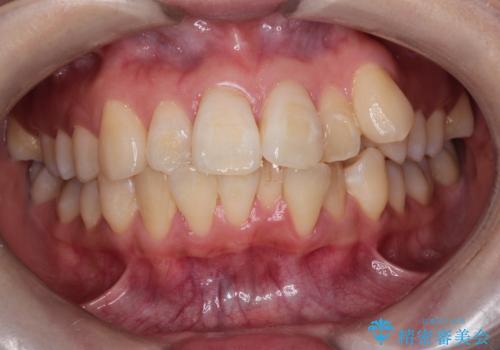

八重歯と正中のズレを解消!目立ちにくいワイヤー矯正で美しい歯並びへ

- 八重歯(叢生)と、上下の歯の中心線(正中)がずれていることを主訴にご来院されました。精密な検査の結果、歯列全体のスペースが大幅に不足しており、八重歯を正しい位置に配列し、正中のズレを改善するためには、上下左右の第一小臼歯を抜歯する必要があると診断。装置には、目立ちにくい審美ワイヤーを使用し、見た目を気にせず、機能性と審美性が完璧に整った咬み合わせを目指す治療計画を立案しました。

今回の矯正治療では、まず計画通り上下左右の小臼歯4本を抜歯し、八重歯や正中のズレを解消するための十分なスペースを確保しました。装置には、目立ちにくい白いブラケットとワイヤーを使用した審美ワイヤー矯正を採用。